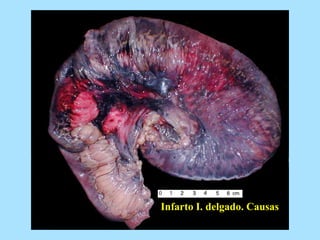

Infarto I. delgado. Causas

La Colitis isquémica (CI) es la forma más

frecuente de isquemia intestinal (70%).

ETIOLOGÍA: OCLUSIVA Y NO OCLUSIVA

1. OCLUSIVA: el resultado de una

obstrucción tanto arterial como venosa.

a. Arterial: émbolo, trombo, traumatismo,

cirugía de aorta, ligadura de AMI sin

buenas colaterales. La cirugía aórtica

selectiva tiene un índice de colitis

isquémica 3-7%.

2. NO OCLUSIVA. La isquemia se suele

desencadenar por un bajo gasto o una

exageración del vasoespasmo